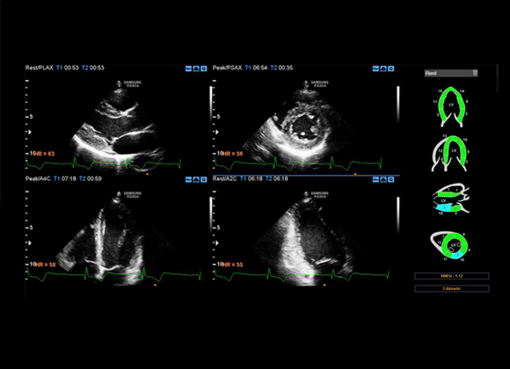

Athena Medica - Centro Diagnostico offre un ambiente professionalmente e tecnologicamente avanzato in continuo aggiornamento, particolarmente attento a garantire qualità e attendibilità dei risultati. Ultimamente il Centro, si è dotato di un nuovo Ecografo, il SAMSUNG RS80A, di ultimissima generazione, con lo scopo di offrire una sempre maggiore qualità ed efficienza diagnostica.

Si tratta di uno strumento dalle prestazioni eccellenti: touch screen da 10,1″ per una migliore usabilità e monitor LED da 18,5″ per una ottimizzazione delle immagini cliniche. Questo Ecofrafo innovativo consente diagnosi rapide e offre maggiore sicurezza durante il trattamento, maggiore precisione diagnostica e un’esperienza migliore per il paziente. Le attività diagnostiche sono garantite dall’utilizzo di tecnologie all’avanguardia e top di gamma, con un’ottima qualità dell’immagine e a bassa esposizione dei pazienti a raggi ionizzanti.

Questa rivoluzionaria tecnologia offre risultati ottimizzati in una varietà di esami ecografici che possono spaziare dall'addome agli organi superficiali come tiroide, collo, parotidi, linfonodi, testicoli e pene, dall'Ecografia muscolo-tendinea a quella transrettale, per poi passare a quella endovaginale, ginecologica, mammaria sino a quella neonatale.

Athena Medica ha sempre posto al centro della propria mission il paziente e le sue esigenze e grazie al nuovo ecografo RS8OA potrà garantire scansioni più approfondite e dettagliate, anche in condizioni diagnostiche tecnicamente complesse, e ottenere diagnosi sempre più tempestive.